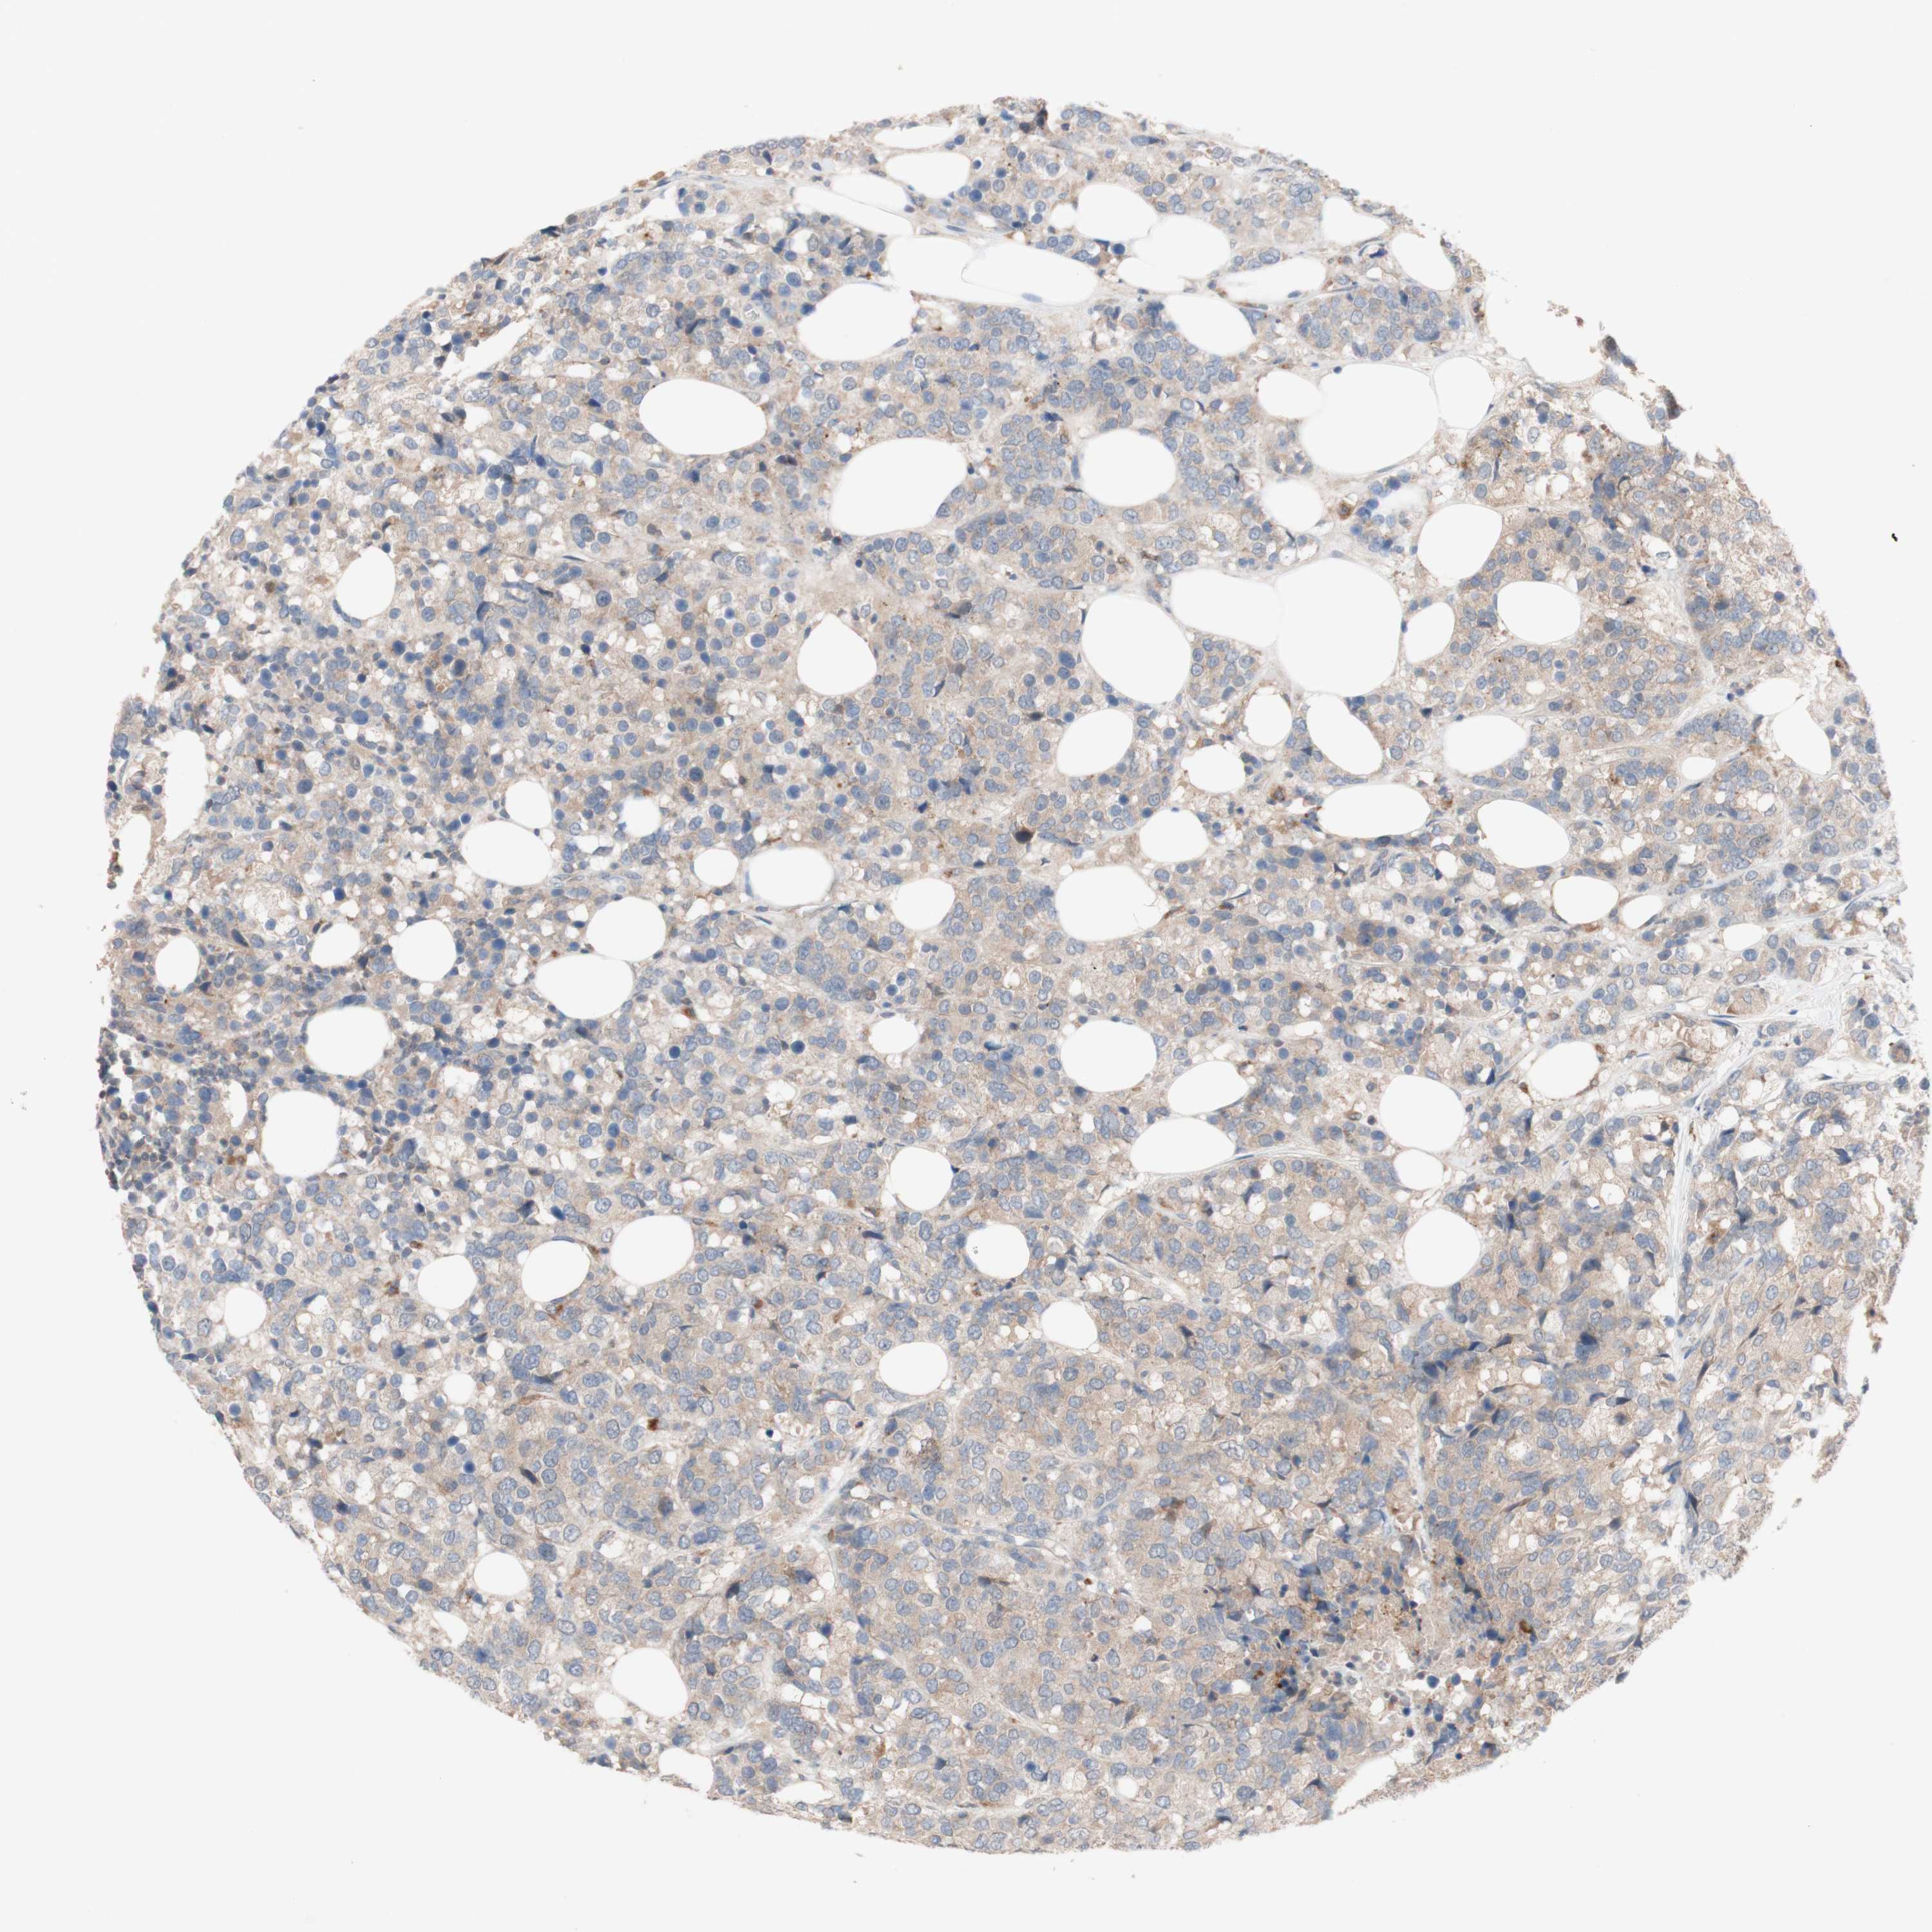

CANCER BREAST CANCER Show tissue menu

BRCA TCGA BRCA VALIDATION PROTEIN EXPRESSION

Breast cancer

Human cancer

PEX2 is not prognostic in Breast Invasive Carcinoma (TCGA)